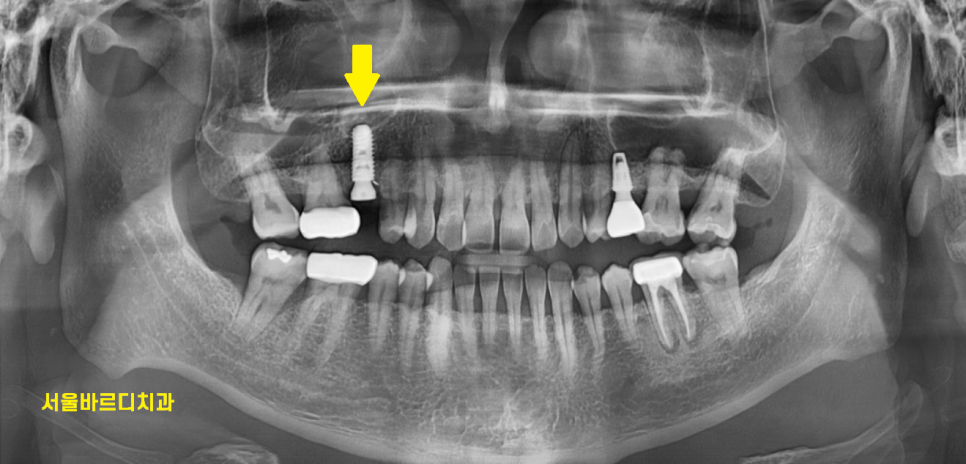

엑스레이를 찍어보았는데

오른쪽 위에 부분에 크게 충치라던가

잇몸 염증은 보이지 않았는데요.

저는 오히려 왼쪽 아래가

더 눈에 잘 들어오더라고요.

240126

동그라미 구멍이 있는 치아가

풍산동 임플란트 한 부위입니다.

구멍이 있는 것은 추후 임플란트에 문제가 생겼을 때

수리하기위함인데

다음 포스팅에서 설명드리겠습니다.